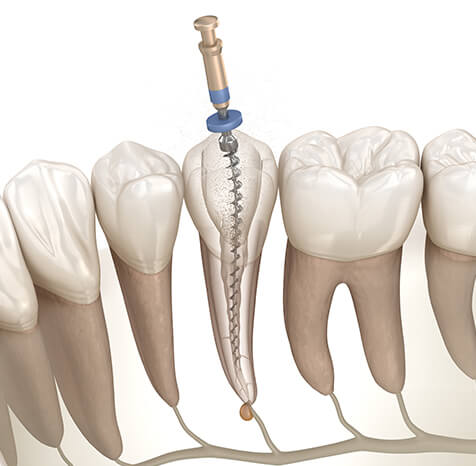

歯の内部から治療する精密根管治療を行っています。

根管治療とは歯の根管の中にある「虫歯に感染した歯の神経」「細菌」「過去に詰めた古い充填材」等を除去していく治療法です。細菌に侵された部分を丁寧に除去・消毒・洗浄を行い、薬液を充填して歯を温存します。